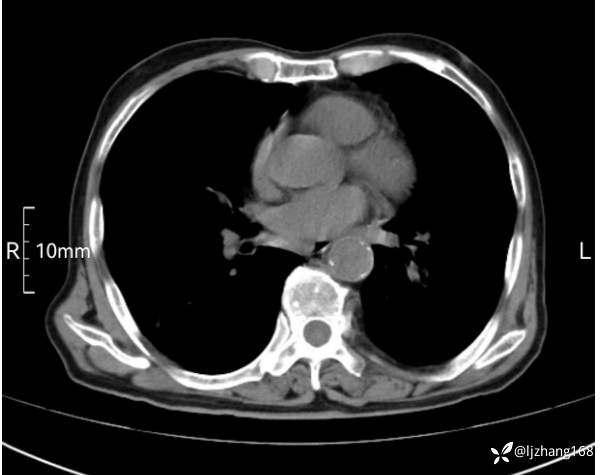

辅助检查:胸部CT:双肺肺气肿,间质性病变,血气分析:PH 7.413, PCO2 29.2mmHg, PO2,81.8mmHg,乳酸 3.3mmol/1,剩余碱-4.0mmol/1,HC03 18.8mmol/1。全血超敏C反应蛋白:超敏C反应蛋白 135.60 mg/L、 白细胞 14x19^9/L,中性粒细胞11.6x10^9/L。